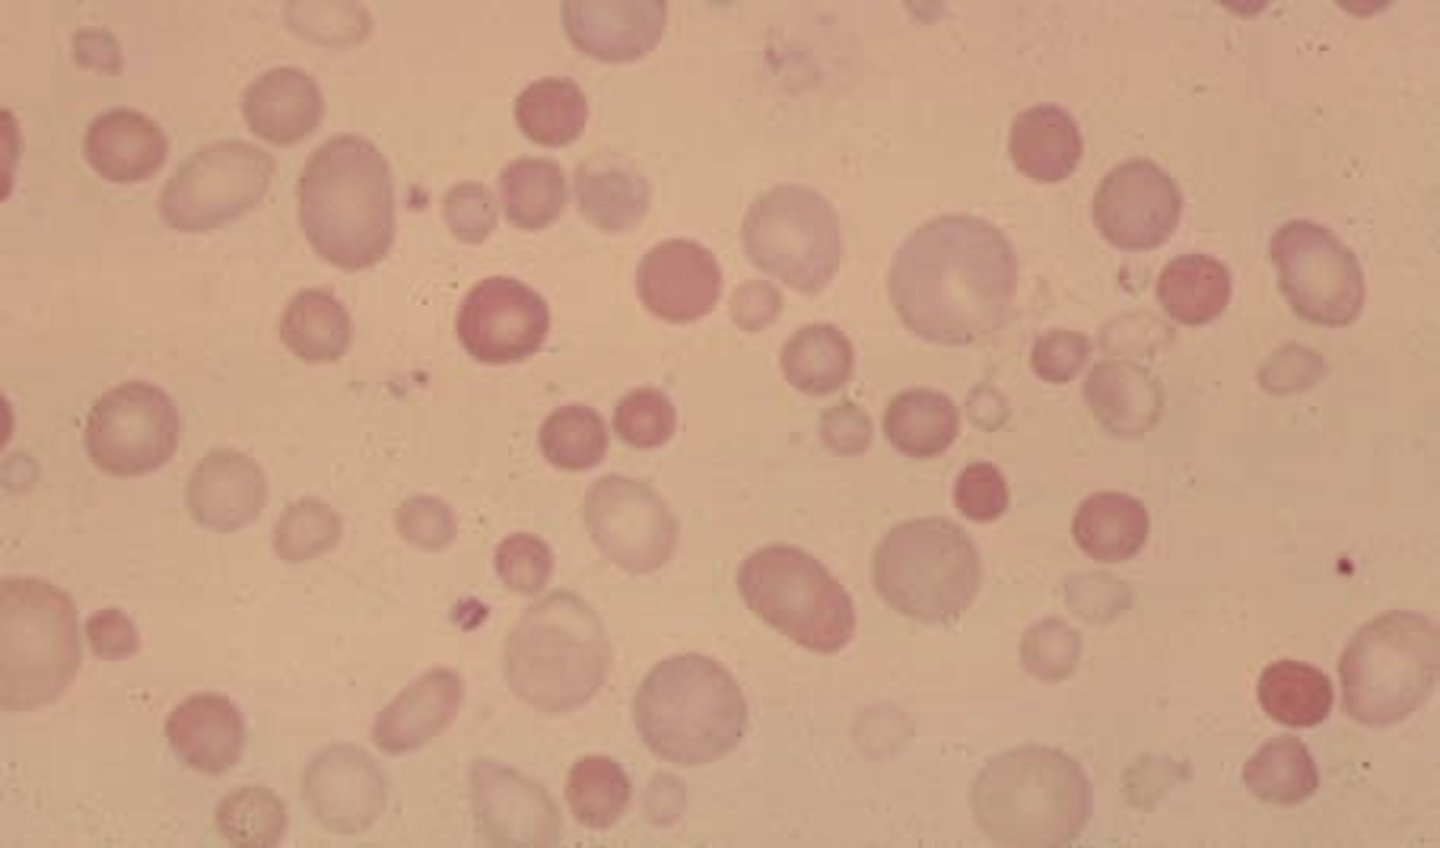

hypochromasia

increased level of central pallor

-decrease hemoglobin concentration